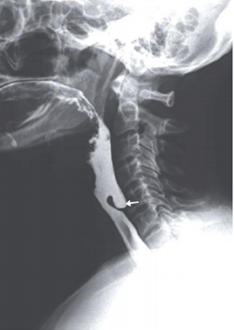

Paciente de 58 anos com queixa de dor cervical, engasgos ao se alimentar e regurgitação de alimentos não digeridos. Realizou exame de radiografia contrastada ao lado:

Em relação ao caso, assinale a alternativa correta.